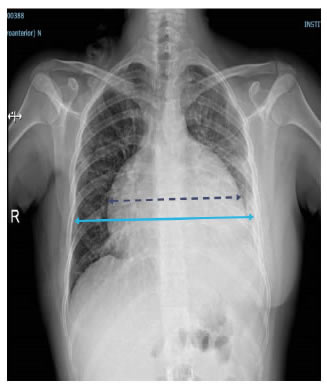

En el electrocardiograma se encontraron signos de bajo voltaje y ausencia de la onda p. En la radiografía de tórax se observó ensanchamiento de la silueta cardiomediastínica y borramiento del ángulo costofrénico izquierdo (figura 1). En la tomografía de tórax (TC), se observó un derrame pericárdico con separación de 3,5 cm entre las hojas del pericardio y un derrame pleural izquierdo (figura 2).

Figura 1.

Radiografía de tórax: derrame pericárdico, ensanchamiento de la silueta

cardiomediastínica (línea punteada) y derrame pleural izquierdo.

Figura 2.

TC de tórax. a. Cortes coronales: derrame pericárdico

homogéneo y sin tabiques. b. Cortes axiales: separación de 3,5 cm

entre las hojas del pericardio (doble flecha). No se observa engrosamiento

del pericardio y hay un escaso derrame pleural izquierdo.